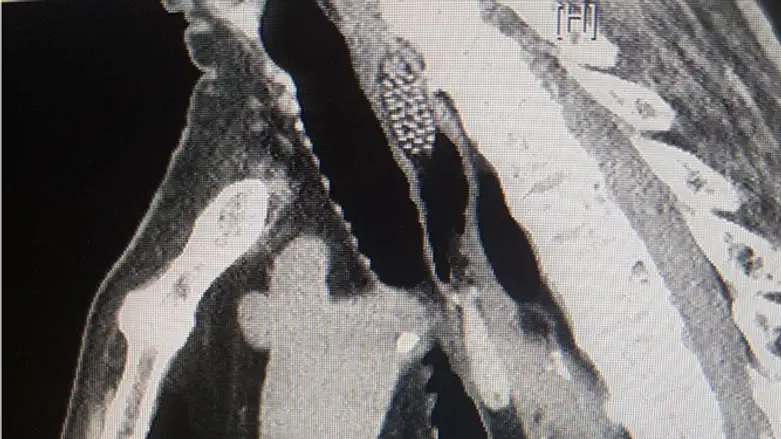

ד"ר רונית בר חיים שטיפלה בו בחדר המיון, הורתה על ביצוע בדיקת C.T. דחופה, בה ניתן היה להבחין בגוף זר שהתברר כמברשת השיניים, כשהיא תקועה בתוך לועו של הקשיש ולא ניתן היה להבחין בה עד לביצוע פעולות דימות.

תוך זמן קצר הועבר הקשיש לחדר ניתוח, שם המתינו לו ד"ר אוהד רונן וד"ר אילי ליוס ממחלקת א.א.ג. ניתוחי ראש וצוואר במרכז הרפואי לגליל, שביצעו פעולה ניתוחית מהירה במהלכה נשלפה מברשת השיניים מבלי שגרמה לנזקים או לסיבוכים במצבו הרפואי של הקשיש, שנותר להשגחה במחלקה ולאחריה שוחרר לביתו.